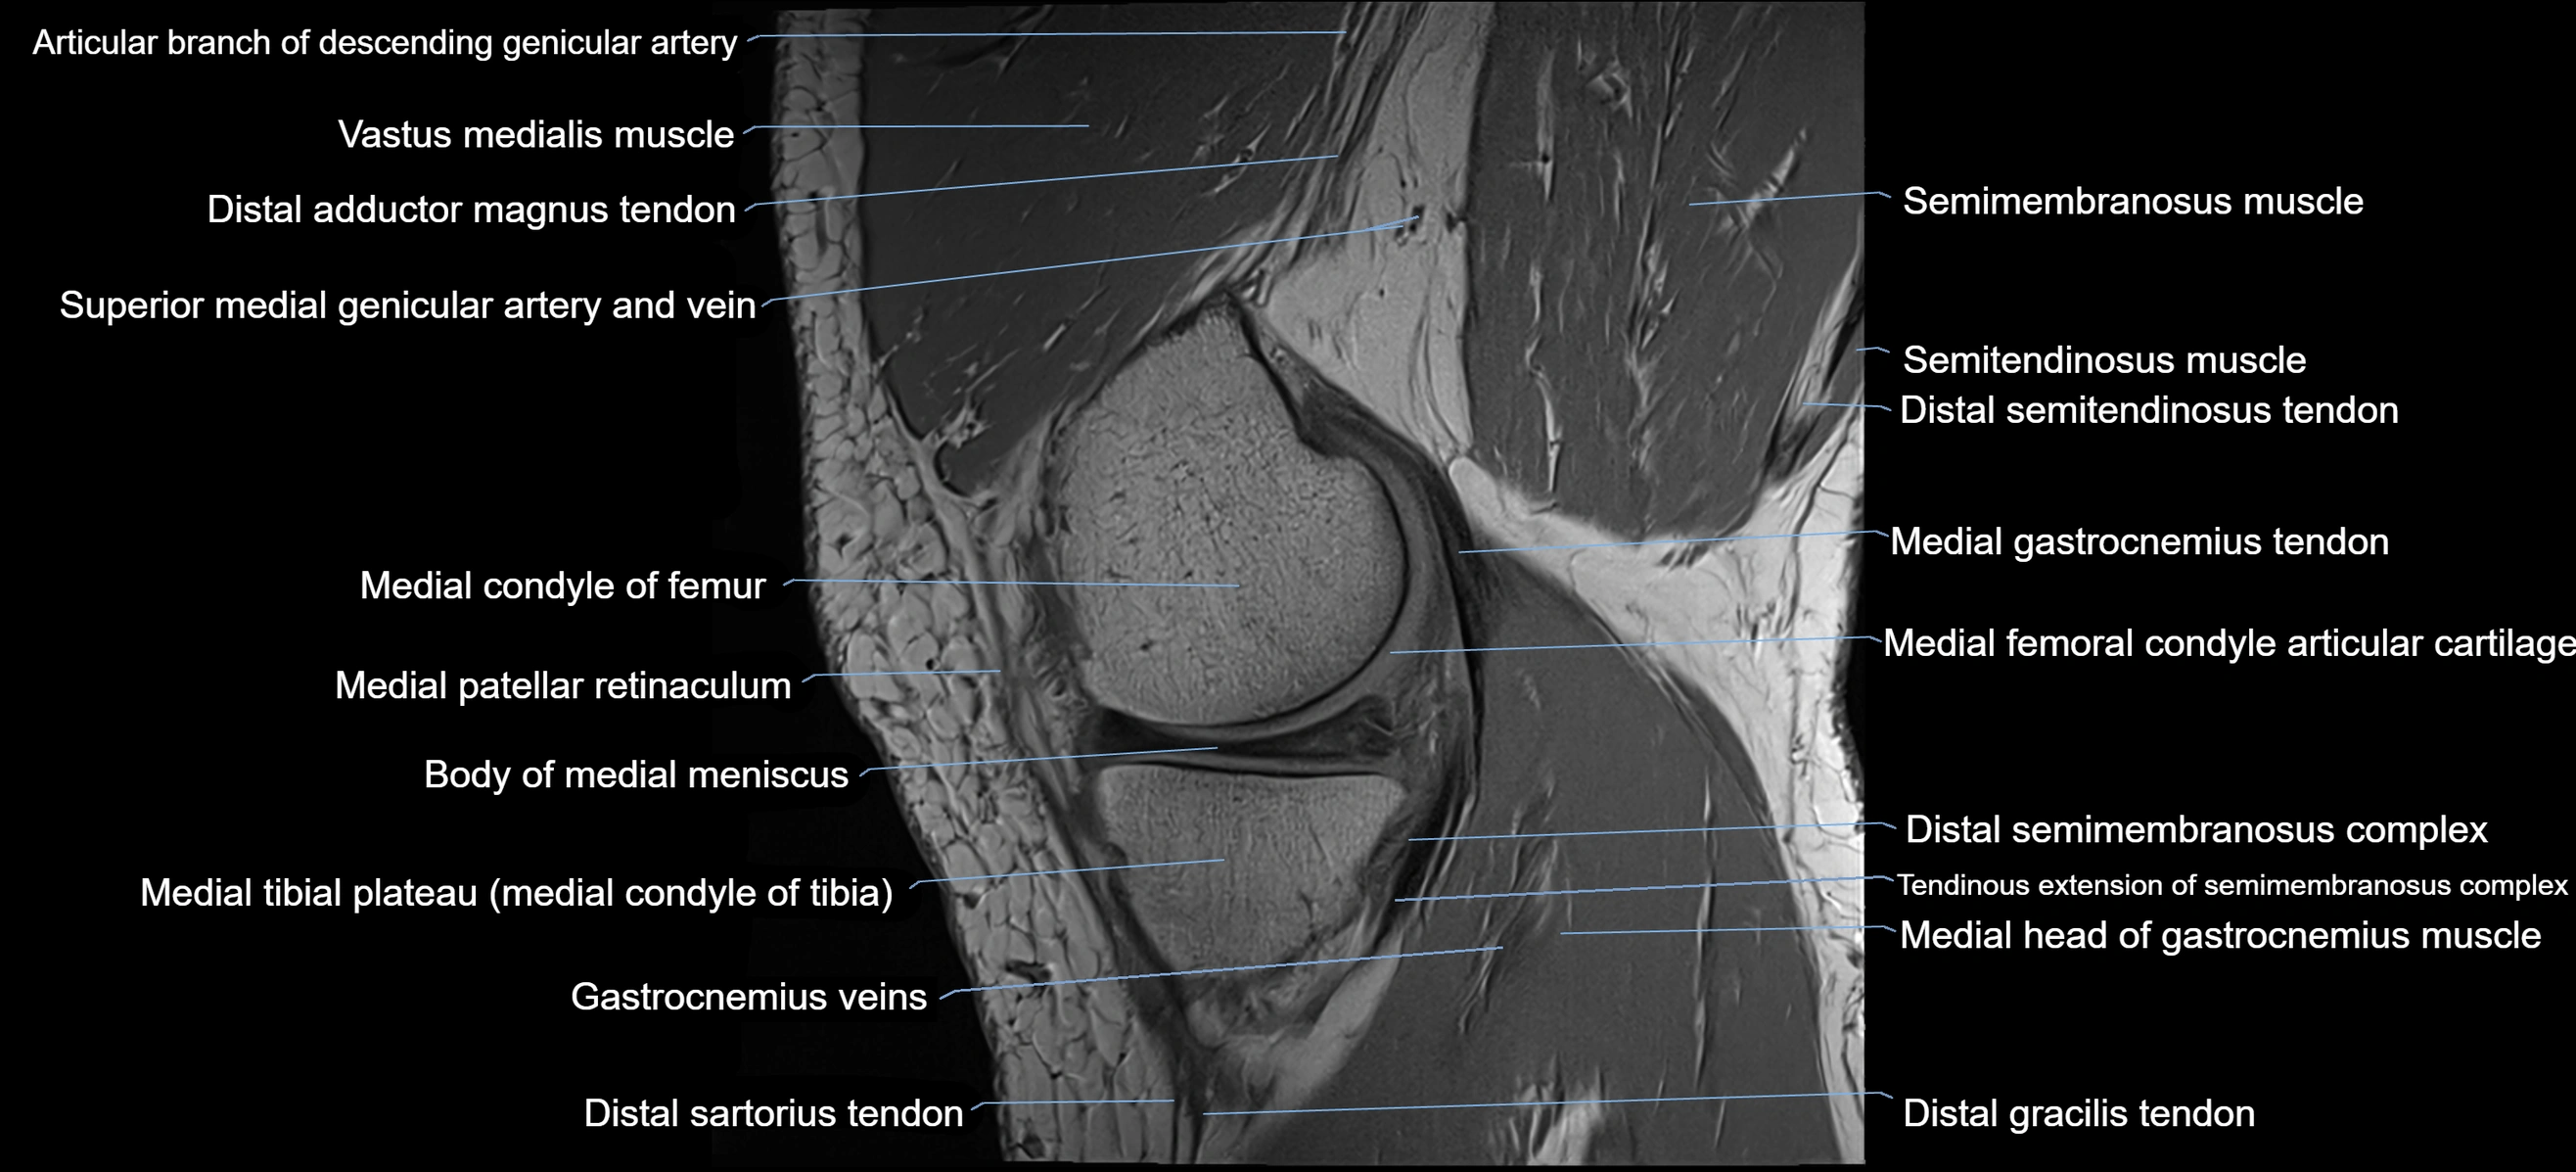

- Body of medial meniscus

- Descending genicular artery (Articular branches)

- Distal adductor magnus tendon

- Distal semitendinosus tendon

- Gracilis tendon (Distal)

- Medial condyle of femur

- Medial gastrocnemius tendon

- Medial head of gastrocnemius muscle

- Medial patellar retinaculum

- Medial tibial plateau

- Sartorius tendon (Distal)

- Semimembranosus muscle

- Semitendinosus muscle

- Superior lateral genicular artery

- Superior medial genicular artery

- Superior medial genicular vein